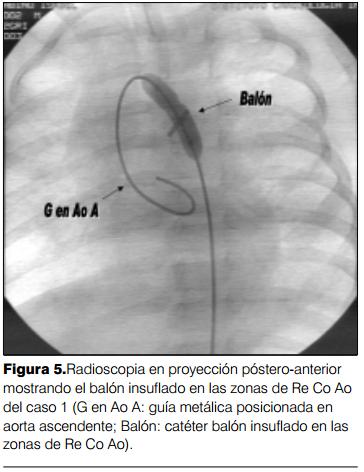

A la edad de 4 meses comienza con polipnea que va en aumento progresivo, comprobándose en el examen clínico los signos de recoartación de aorta. El ecocardiograma confirmó la presencia de recoartación significativa. Se traslada al ICI y se procede a efectuar cateterismo cardíaco que muestra un gradiente de 40 mmHg entre aorta ascendente y aorta descendente, con dos zonas de estenosis, una proximal y otra distal en el puente de vena cava superior izquierda, procediendo a efectuar angioplastia con catéter balón GHOST de 5 x 2 mm, quedando un gradiente residual de 10 mmHg con buena evolución posterior, persistiendo moderada hipertensión arterial pulmonar (en control con ecocardiograma doppler) en un paciente asintomático (figuras 4, 5,y 6).